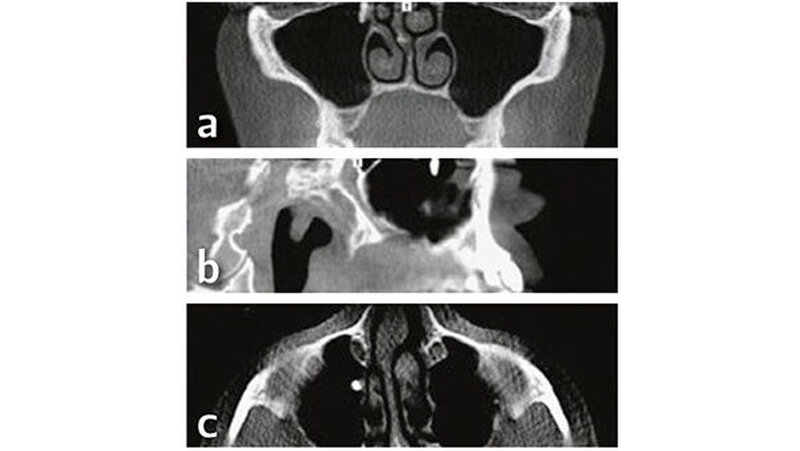

Befund der digitalen Volumentomografie

Röntgenologisch (Abb. 1) zeigen sich auf der OPT-Ansicht ein dental und ossär unauffälliger Befund und eine gut belüftete, nicht verschattete rechte Kieferhöhle. Der Verdacht eines Wurzelrests in regio 17 bestätigt sich in dieser Darstellung nicht. Erst nach genauerer Betrachtung der axialen,coronalen und sagittalen Bildebenen des DVT konnte eine zahndichte Verschattung regio Ostium naturale des Sinus maxillaris dargestellt werden, welches kaudal in das Infundibulum ethmoidale und kranial in den Hiatussemilunaris mündet (Abb. 2).